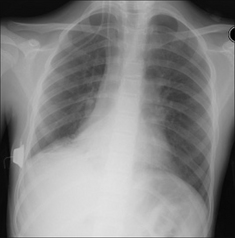

Figure 28.5 Acute dyspnoea. No obvious CXR abnormality. Apply Golden Rule 1—clinical details are crucial. History of left sided pleuritic pain. Apply Golden Rule 2—ask the CXR a specific question…and Golden Rule 3—you only look for what you know. CXR conclusion—careful inspection of the left apex reveals a shallow pneumothorax. The arrow indicates the visceral pleura.